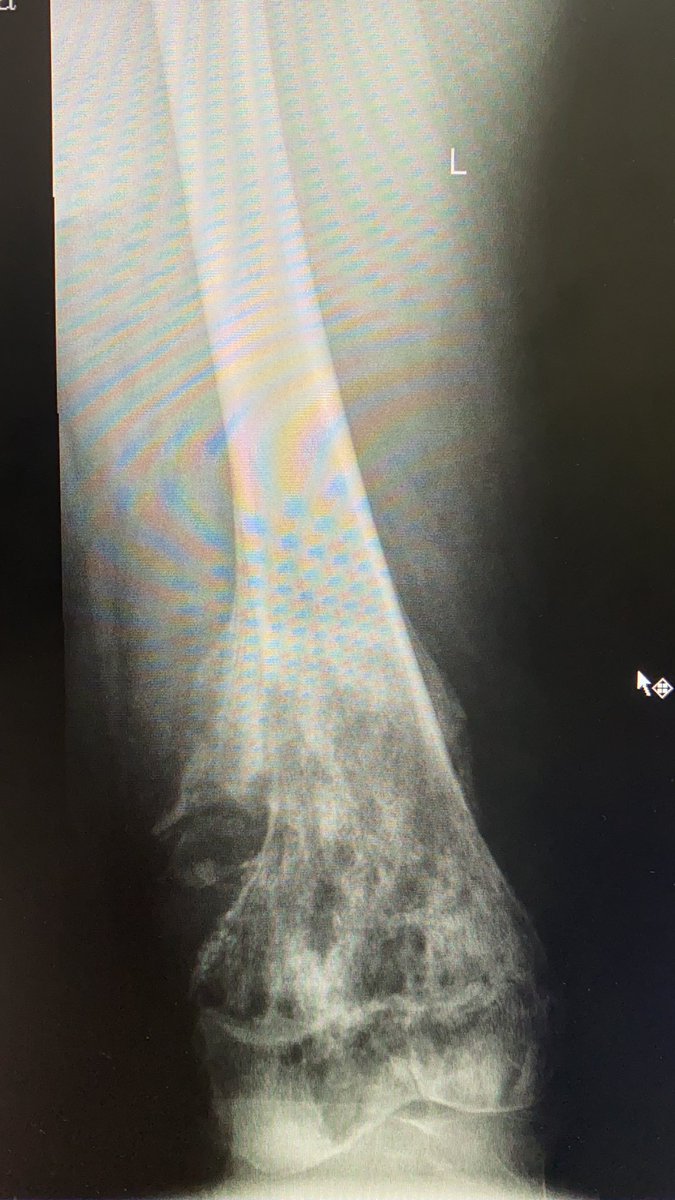

من المشاكل الاخرى مع التامين عدم الموافقة على اجراء كامل الفحوصات الطبية للاورام العظميه قبل الخدعة بحجة انه لا يوجد ما يثبت ان هناك ورم خبيث رغم ان اي طبيب عظام سنة اولى في التخصص يستطيع ان يعرف ان المرض خبيث من اول نظرة للأشعة العادية